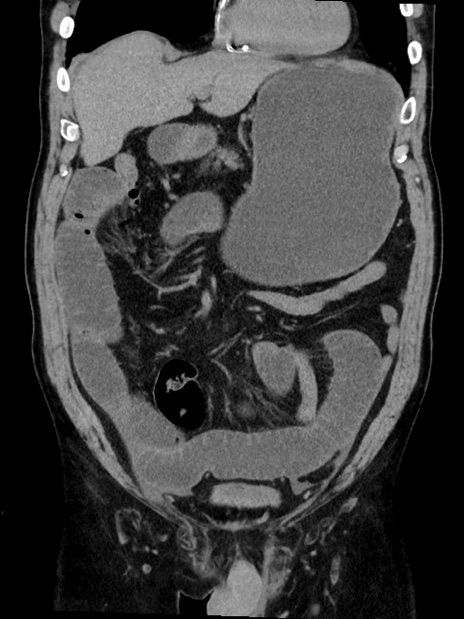

症例35(冠状断像)

【症例】70歳代 男性

【主訴】腹部膨満、嘔吐

【現病歴】昨日より腹部膨満感出現。本日増悪し、仙痛出現。嘔吐あり、受診。

【既往歴】糖尿病、胆摘後

【身体所見】BP 149/80mmHg、HR 74/min、BT 35.9℃、腹部:膨満、軟、圧痛なし。腸雑音減弱あり。上腹部正中切開瘢痕あり。

【データ】WBC 13500、CRP 1.72